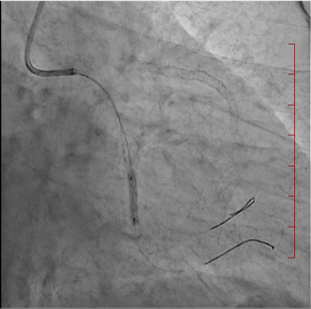

経皮的冠動脈形成術

経皮的冠動脈形成術とは、狭くなった、あるいは詰まった冠動脈(心臓の筋肉に血流を送る血管) に対し、カテーテルを用いる治療法の総称です。バルーンやステントを使用して冠動脈を広げる治療です。

| 治療前 | ステント留置中 | 治療後 |